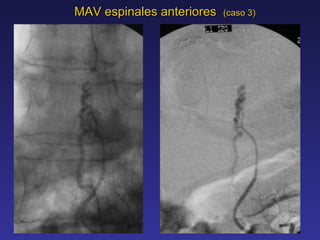

MAV espinales anteriores  (caso 3) Hombre 54 anos de edad con antecedentes de dolicoectasia bicarotidea y acromegalia detenida Mientras iba manejando presenta dolor intenso en la espalda y flanco izq. Llega a Servicio de Urgencia en Concepcion en Septiembre 2000 y por retencion urinaria es evaluado por Urologo realizandole intervencion prostatica endoscopica de Urgencia El paciente sentia menos sus piernas por lo que consulta y se traslada a Santiago Se encuentra un examen neurologico normal a su ingreso tres dias despues. Sonda Foley postoperatoria. RM muestra MAV T-10 anterior